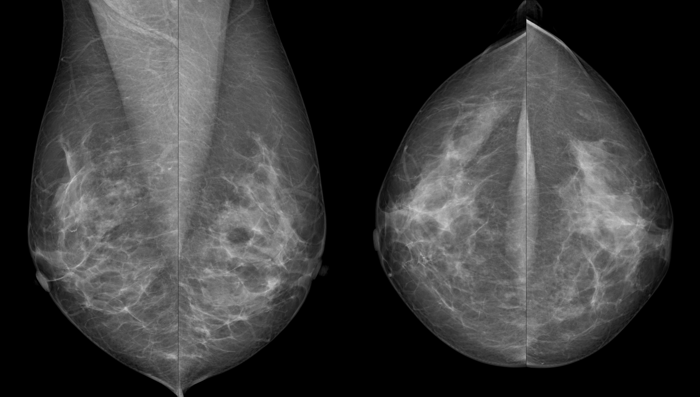

Von jeder Brust werden üblicherweise zwei Aufnahmen - jeweils von oben nach unten (cranio-caudale Aufnahme) und schräg von innen nach außen (medio-laterale oblique Aufnahme) - angefertigt. Die Brust wird dabei in eine Vorrichtung eingespannt und komprimiert:

Die cc-Aufnahme wird immer so dargestellt, dass die Außenseite der Brust im Bild oben liegt.

können die Brustabschnitte in der Nähe der Achsel besser dargestellt werden.

Warum werden von jeder Brust zwei Aufnahmen gemacht?

Die Brust ist ein dreidimensionales Organ, die Aufnahmen sind hingegen flach. Um die sichtbaren Strukturen räumlich richtig einordnen zu können, sind daher zwei Aufnahmen in verschiedenen Ebenen notwendig.